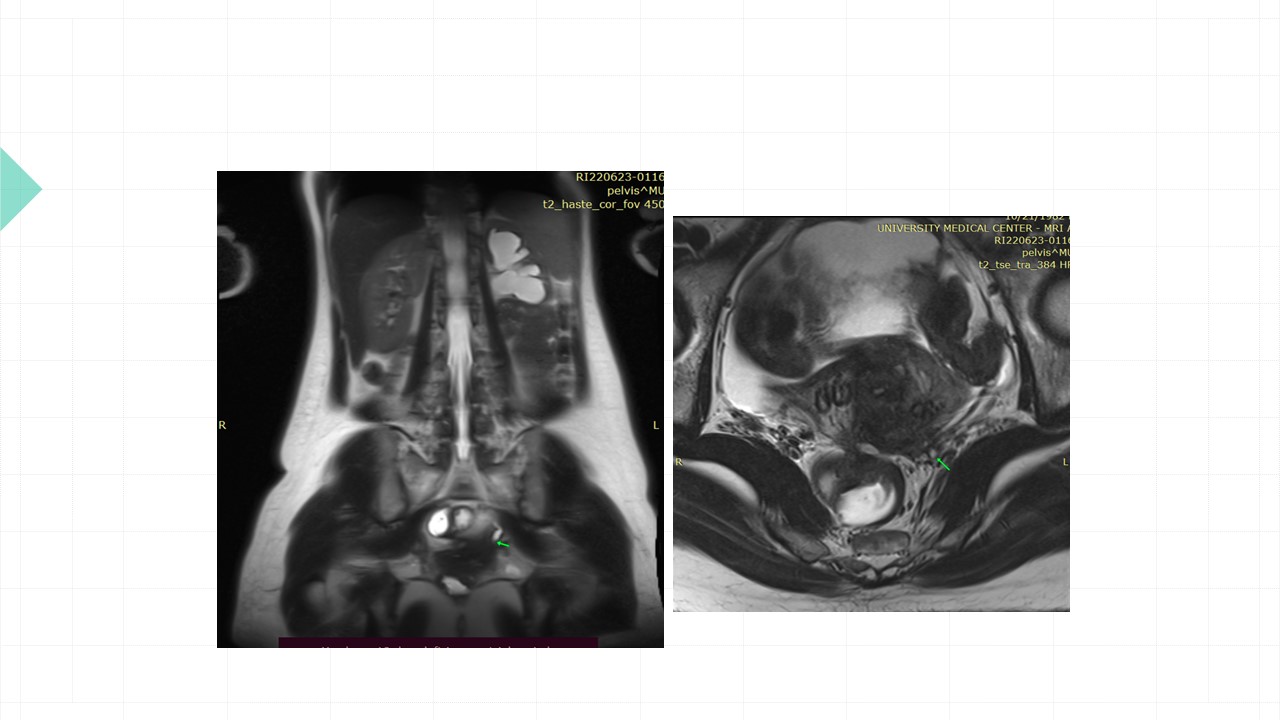

Vai trò cộng hưởng từ trong đánh giá lạc nội mạc tử cung

Từ khóa: Vai trò cộng hưởng từ trong đánh giá lạc nội mạc tử cung